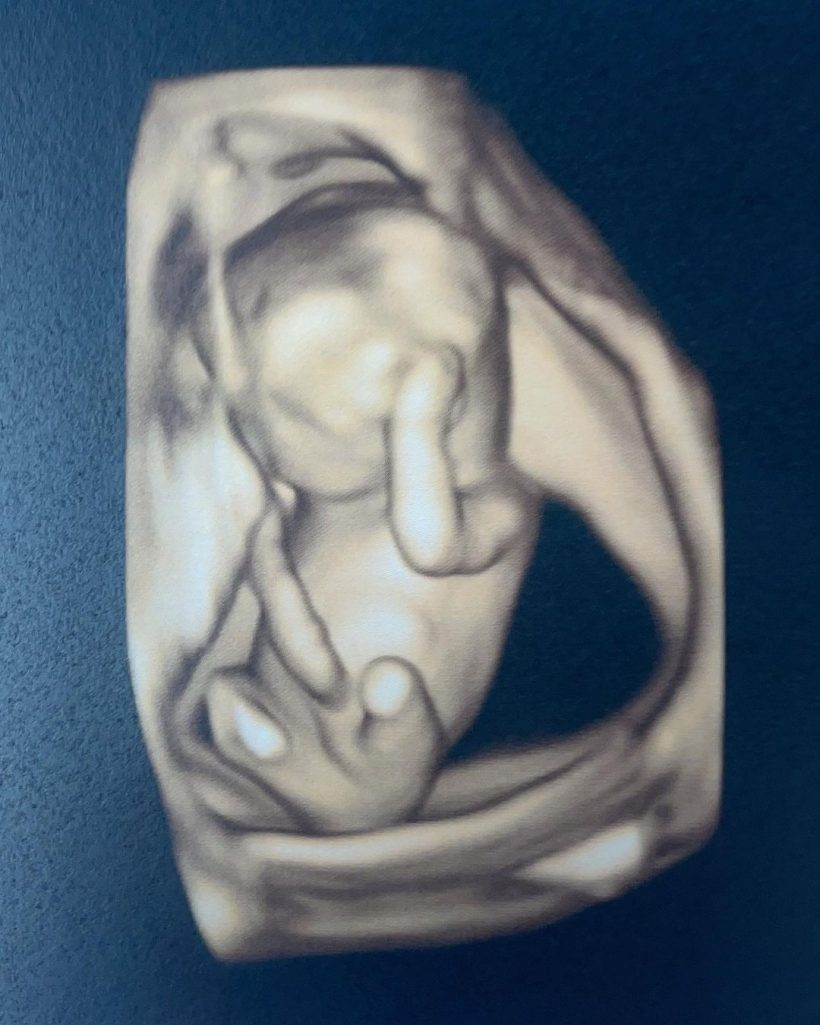

ล่าสุด หนูเล็ก เผยภาพอัลตราซาวนด์ลูกน้อยในครรภ์ พร้อมเฉลยเพศลูก ว่า “เพศลูก ผู้ชายนะคร้า ผงาด โชว์แต่เด็กเล้ยยยยย “

Cr_ig: nuulekk_benjawan